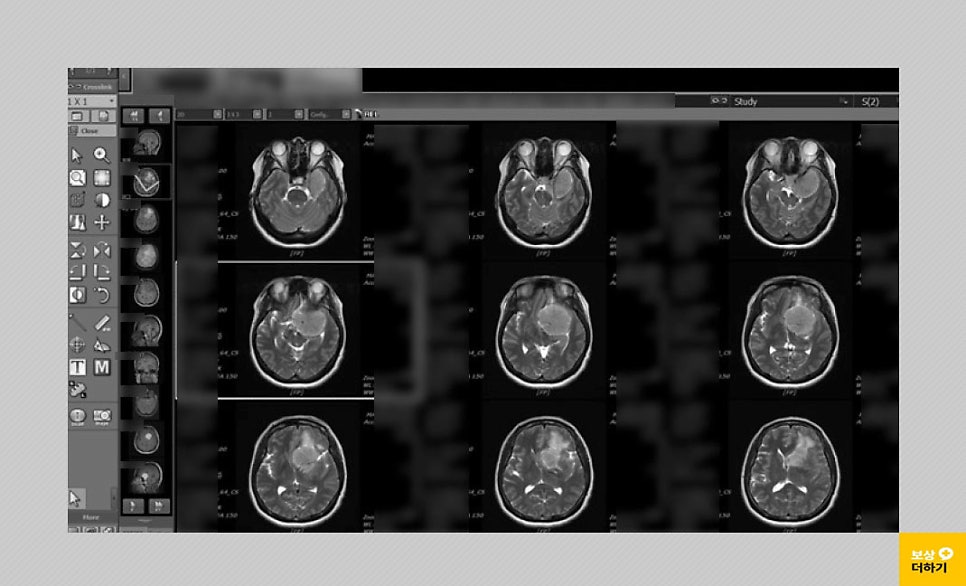

50대 여성이신 박 00 님은 어느 날부터 몸의 불편함을 느끼셨는데요. 두통과 함께 가장 이상함을 느낀 건 왼쪽 눈의 시력이 떨어지는 것이었습니다. 이에 따라 내원을 하셔서 뇌 MRI, 혈관 조영술 등 검사를 받으셨어요.

검사 결과 좌측 측두부, 접형부에 발병한 5.5cm 크기의 뇌수막종이었습니다. 시신경, 내경동맥, 뇌간을 압박해서 종양 완전 제거는 어렵고 수차례 수술, 방사선 치료가 필요하다고 판단되었습니다. * 수술: 개두술 및 두개 내 종양 절제술 받으셨습니다.